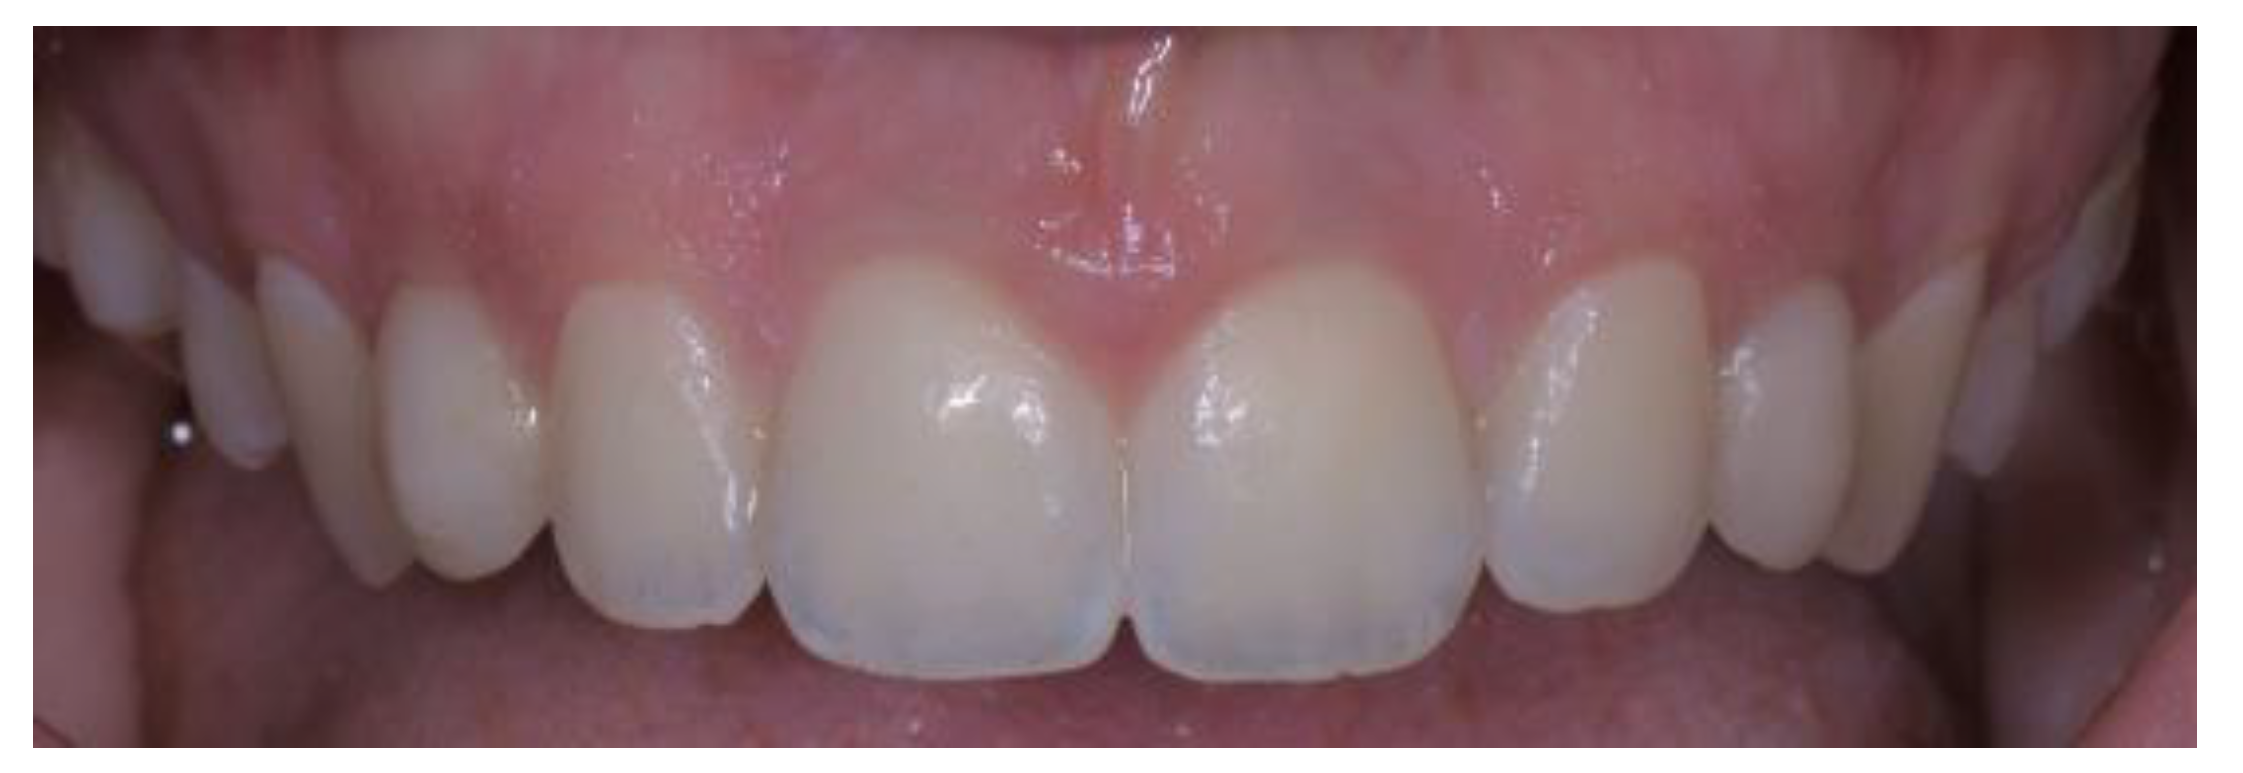

2.5. Individual Cases Description

- Case 1:

- Case 2:

- Case 3:

- Case 4:

- Case 5: